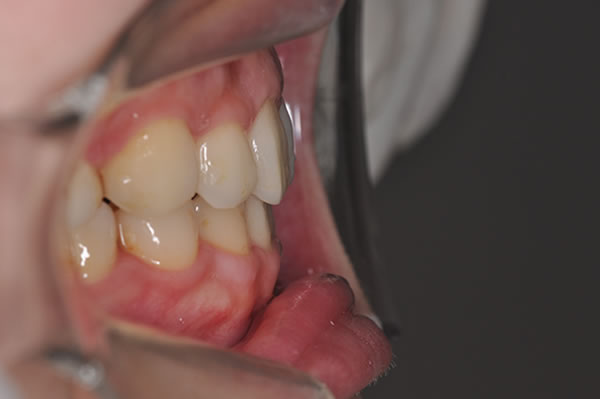

上顎前突症の治療例

上顎前突症(出っ歯)の矯正症例 ケース01

| 治療前(初診) | 治療後 | |